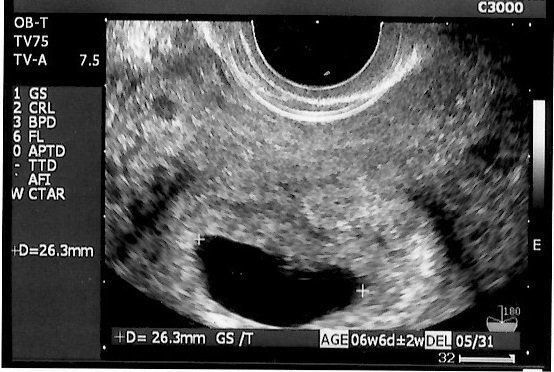

妊娠6週目のエコー写真 分娩する病院を決定

体調は何も変化はないので、相変わらず妊娠している実感はわかず。エコー画像を見るまで赤ちゃんが無事おなかの中で育っているかどうか不安でいっぱいでした。不妊治療専門クリニックから分娩可能な病院を紹介しているリストをもらうと、近隣で一番大きな大学病院の産科に分娩予約しました。高齢出産だったため、万一のことを考えて設備の整った大学病院を選択しました。